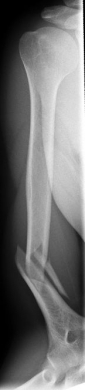

Picture: Here you can see a completely shifted upper arm fracture with a strong bend of the axis. First the operative treatment was performed by repositioning the bone and internal splinting of the fracture with a medullary nail.